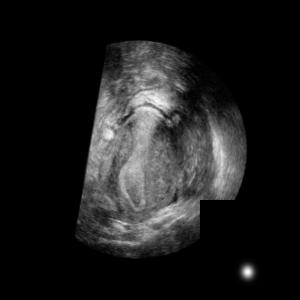

Standard plane (SP) localization is essential in routine clinical ultrasound (US) diagnosis. Compared to 2D US, 3D US can acquire multiple view planes in one scan and provide complete anatomy with the addition of coronal plane. However, manually navigating SPs in 3D US is laborious and biased due to the orientation variability and huge search space. In this study, we introduce a novel reinforcement learning (RL) framework for automatic SP localization in 3D US. Our contribution is three-fold. First, we formulate SP localization in 3D US as a tangent-point-based problem in RL to restructure the action space and significantly reduce the search space. Second, we design an auxiliary task learning strategy to enhance the model's ability to recognize subtle differences crossing Non-SPs and SPs in plane search. Finally, we propose a spatial-anatomical reward to effectively guide learning trajectories by exploiting spatial and anatomical information simultaneously. We explore the efficacy of our approach on localizing four SPs on uterus and fetal brain datasets. The experiments indicate that our approach achieves a high localization accuracy as well as robust performance.

翻译:标准平面( SP) 本地化对于常规临床超声( US) 诊断至关重要 。 与 2D US 相比, 3D US 可以在一次扫描中获得多个查看平面, 并提供完整的剖面, 加上冠冕平面 。 然而, 3D US 人工导航 SP 是困难和偏颇的, 因为方向变化和搜索空间巨大。 在此研究中, 我们引入了一个新的强化学习框架( RL ), 用于3D US 的自动超声波( US) 。 我们的贡献是三维美国 。 首先, 我们将 SP 本地化作为 RL 的正切点问题, 以重组行动空间并显著缩小搜索空间 。 其次, 我们设计了一个辅助任务学习战略, 以增强模型在搜索中识别非 SP 和 SP SP 的微妙差异的能力 。 最后, 我们提出一个空间分析奖赏, 以有效指导在 3D 中利用 空间 和 解剖面信息 学习轨迹 。 我们探索了 4 本地化 4 4 方法的有效性 。